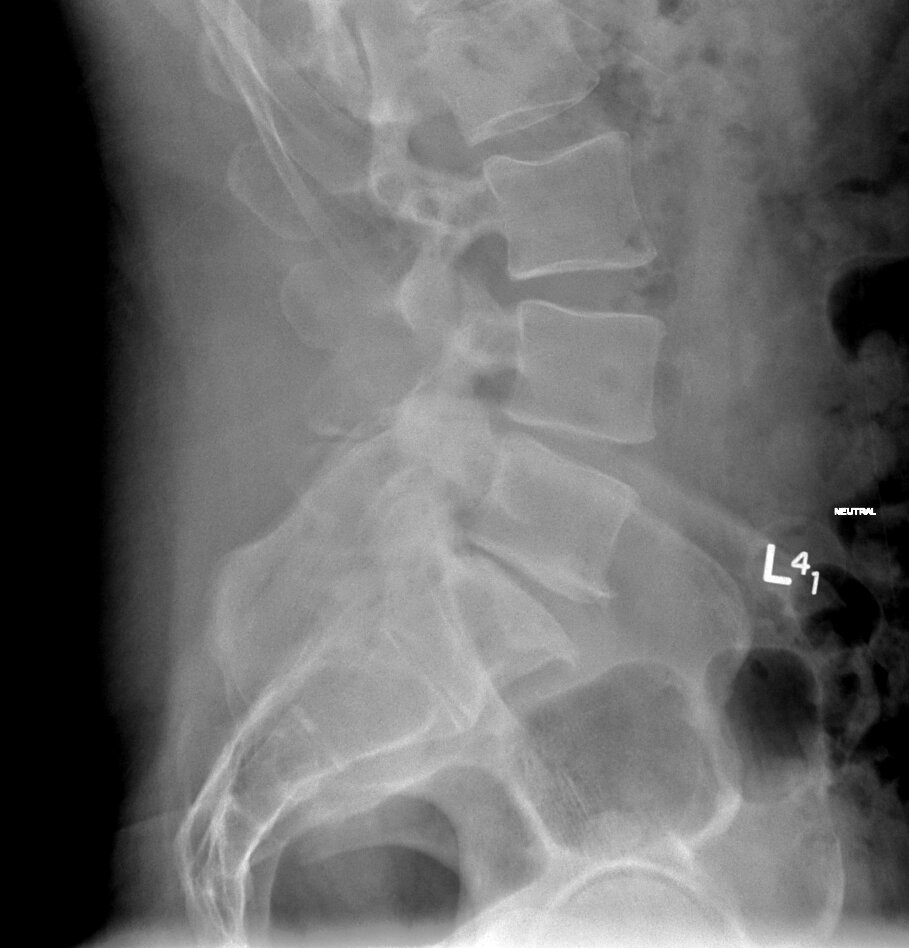

- Degenerative disc disease causing disc collapse with compression of the nerves and back pain

- Spondylolisthesis, which is instability between the spine bones, when two vertebrae shift next to each other

- Recurrent disc herniation

At the spine levels above L4-5, anterior approach to the spine may also be complicated. In those cases, an LLIF, Lateral Lumbar Interbody Fusion, may be an option. TLIF, Transforaminal Lumbar Interbody Fusion, a surgery done through the back, may be used when neither ALIF nor LLIF are possible.

The spine levels at L4-5 and L5-S1 are most commonly addressed with ALIF. If you have a kind of pathology at those levels that may require fusion and to discuss your case and see what treatments are most appropriate for you, request an appointment for a face-to-face consultation.